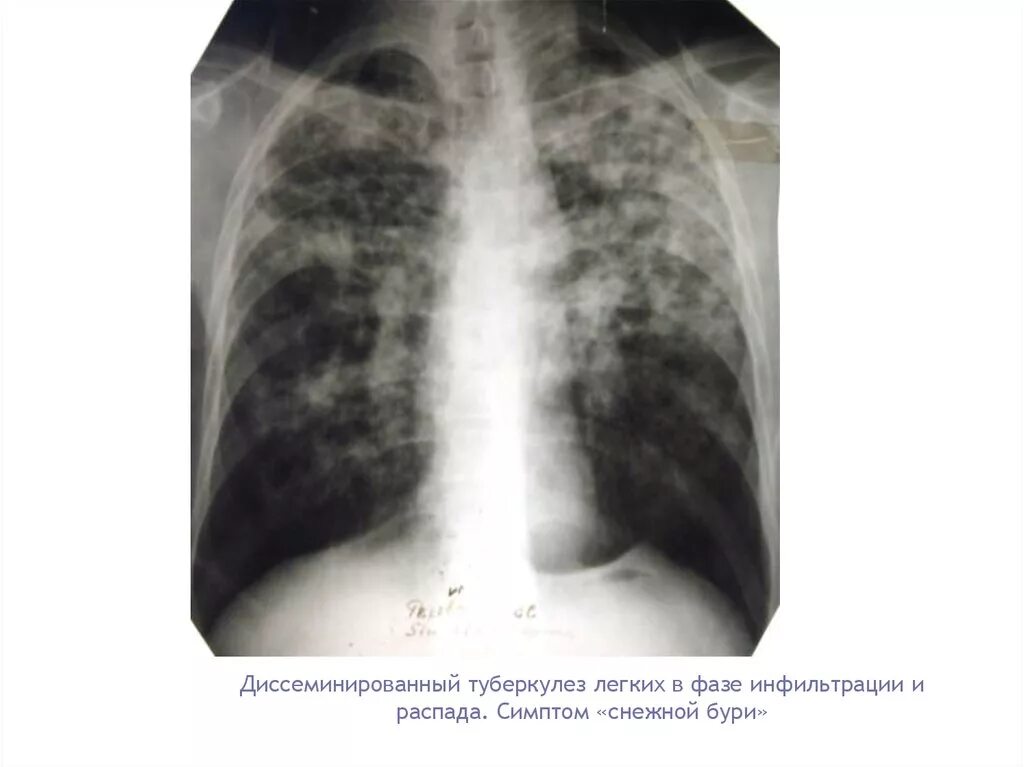

Стадия инфильтрации легких